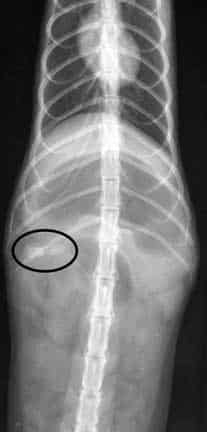

Here is the answer to the radiographs at the beginning of this page. The foreign body is circled.

On the VD view the mildly opaque foreign body is at the beginning of the small intestines called the duodenum

The arrow points to the circular FB on the lateral view in the same location. Note the dark area that says small intestine. This dark area is gas, because the foreign body is causing an ileus, and the intestine is filling up with gas and distend because the normal peristalsis is interrupted.